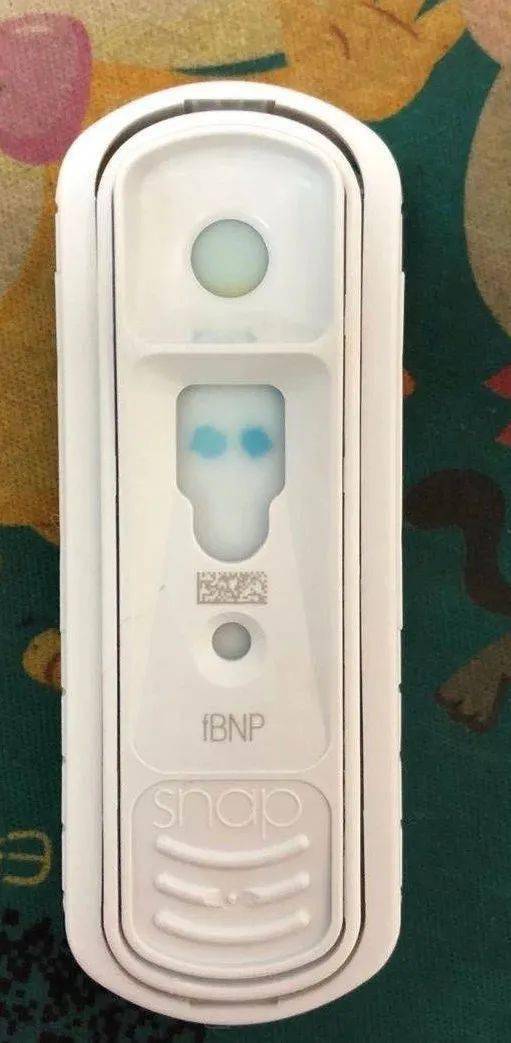

关于pro bnp,快速检测猫咪心脏健康的途径

图片尺寸1080x1080

肥厚性心肌病养猫人必须知道的一种疾病

图片尺寸511x1043